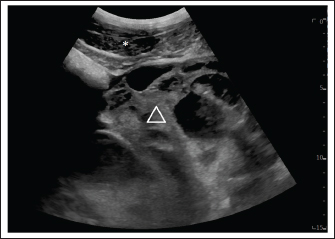

Immediately after a 30 cm long ventral midline incision, the GCT was visible in the surgical field (Fig. 3). It extended across the abdomen from the right to the left side. On the right side, it was adjacent to the caecum and the ascending colon, and the small intestine was visible underneath the GCT. Cranially, the GCT extended to the stomach and the caudal part of the lateral right lobe of the liver. Following the caudal surface of the GCT, the association of the GCT with the right ovary was ascertained. The right uterine horn and oviduct were palpable. Exteriorization of any part of the intestine was not possible due to the dimension and weight of the GCT. The ovarian pedicle and the uterus horn were also positioned underneath the GCT and could not be exteriorized. Due to the size of the mass, the only way to exteriorize the GCT and to ligate blood vessels was after its dissection into smaller segments. For the procedure, a tenotomy knife was used to transect the GCT in its length and approximately 1/3 of the mass was removed. Dissection of the GCT was performed blindly under manual control. The partial resection of the GCT was started in the ventral part of the GCT, which was visible after the ventral midline incision. Following the structure of the GCT, the dissection was continued dorsally, in the sagittal plane of the GCT. During the dissection, the bowel was protected under the hand of the surgeon performing the dissection, and an assistant provided support by removing the bowel from the incision line. The consistency of the GCT was firm and hard. The last centimeter of the dissected GCT, which was still connected to the main GCT, was bluntly separated by hand to avoid damage to the organs by the tenotomy knife.

Fig. 3. Surgical view following ventral midline laparotomy with the horse in dorsal recumbency. Cranial is at the bottom of the image. The GCT is seen against the abdominal wall (arrow). A small segment of the small intestine was visible (triangle). The dimension of the tumor did not allow any exteriorization from the large or small intestine and any manipulation was possible.